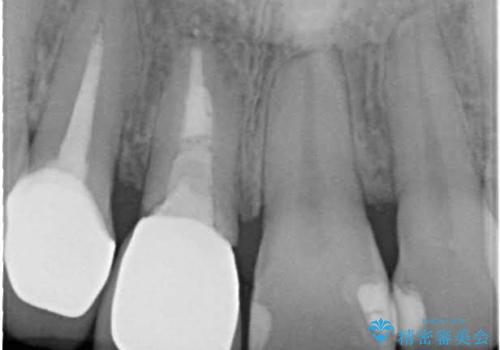

- 抜歯前提の歯根挺出により保存の難しい前歯を抜去

→根管治療のやり直しなどを経て、ブリッジを製作する。

古いかぶせ物は土台ごと歯から脱落してしまっており、歯の内面には複数の亀裂が入っている状態でした。残存歯質が非箔であることと、動揺の程度から、やむを得ず抜歯→ブリッジという方法を選択していただき、歯根挺出を用いることでなるべく前歯の骨の陥没を防ぎ、ブリッジを製作しました。